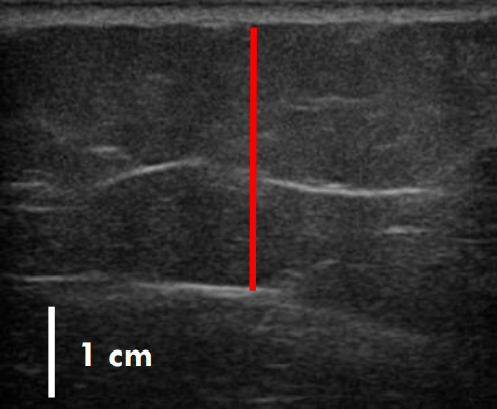

위 사례도 초음파 비교 사진을 보도록 할게요.

트루스컬프 아이디 시술 전, 12주 후

초음파를 비교한 사진입니다.

위 사례의 경우 지방량이 워낙 많다 보니 시술 후 겉으로 드러난 변화는 적었으나 실제로 감소한 지방량은 상당히 많았습니다.

시술 전과 비교했을 때 약 31% 정도 지방이 감소했습니다.

복부, 옆구리살이 너무 많은 경우 실제 눈에 보이는 것보다 내부에 쌓여있는 지방이 두터운 경우가 많아 시술을 해도 큰 변화를 보이지 않는 경우가 많은데요. 실제로 시술 후 큰 변화가 없어 실망하는 분들도 많지만 위와 같이 초음파 검사를 통해 속을 들여다보면 상당 부분 지방이 감소한 것을 확인할 수 있습니다.